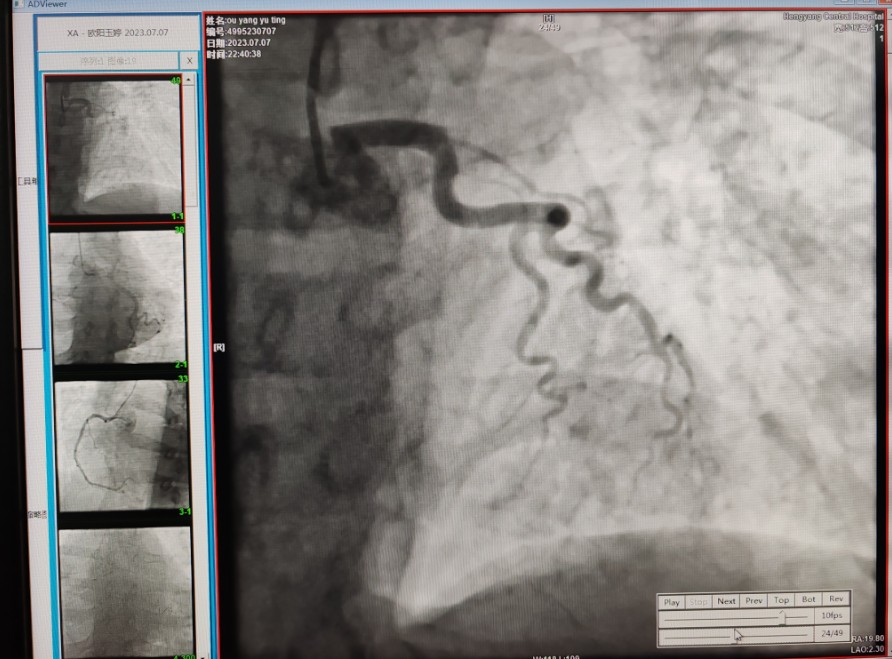

22:29分患者經(jīng)院內(nèi)綠色通道送達(dá)導(dǎo)管室,手術(shù)由雷剛副主任醫(yī)師主刀,楊繼賀副主任醫(yī)師為第一助手,介入技師及護(hù)士密切配合,聞?dòng)嵍鴣淼内w慶禧主任醫(yī)師坐鎮(zhèn)協(xié)調(diào)指揮。22:37分手術(shù)開始,冠脈造影顯示心臟上最重要的一條冠狀動(dòng)脈-前降支開口齊頭閉塞,血管粗大且血栓高負(fù)荷,非??简?yàn)介入術(shù)者的手術(shù)能力,一旦發(fā)生冠脈無復(fù)流或操作不慎血栓帶入回旋支導(dǎo)致循環(huán)崩潰,病人幾乎無生還希望;此時(shí),患者手術(shù)臺上仍持續(xù)胸痛,且血氧飽和度在高流量吸氧狀態(tài)下不到80%,雷剛副主任醫(yī)師一方面指揮鎮(zhèn)靜鎮(zhèn)痛及抗心衰治療,一方面緊急啟用IABP(主動(dòng)脈球囊反搏),然后精細(xì)操控細(xì)如發(fā)絲的介入導(dǎo)絲迅速通過病變,并予冠脈球囊擴(kuò)張、冠脈內(nèi)溶栓、抗痙攣藥物使用、植入冠脈支架,最終成功開通“罪犯”血管,且無手術(shù)并發(fā)癥發(fā)生,整個(gè)過程張弛有度、快慢結(jié)合、一氣呵成?;颊咝g(shù)后胸痛明顯好轉(zhuǎn),血氧飽和度上升至96%,術(shù)后1天轉(zhuǎn)出監(jiān)護(hù)病房,第3天拔出IABP,目前已康復(fù)出院。